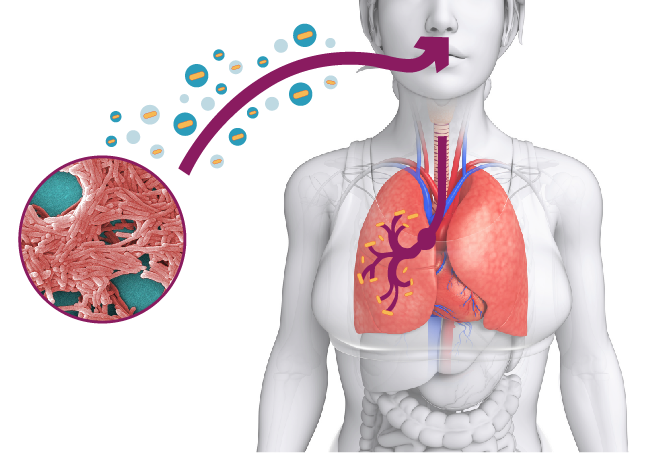

LEGIONELLA, COME PREVENIRLA

La Legionella, come si forma e contagia l’uomo.

Regole di igiene da seguire per prevenirla…